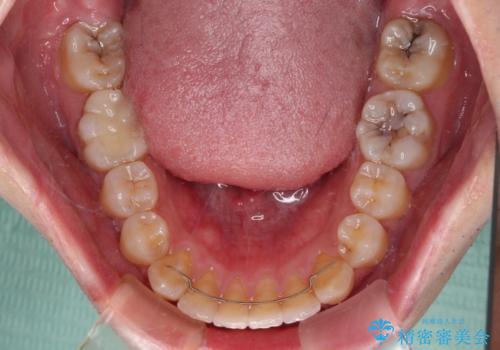

下顎前歯が思っていた以上に動きが悪く、想定よりも期間がかかってしまいました。

矯正治療後には気になっていた銀歯をセラミックで自然な色に仕上げました。